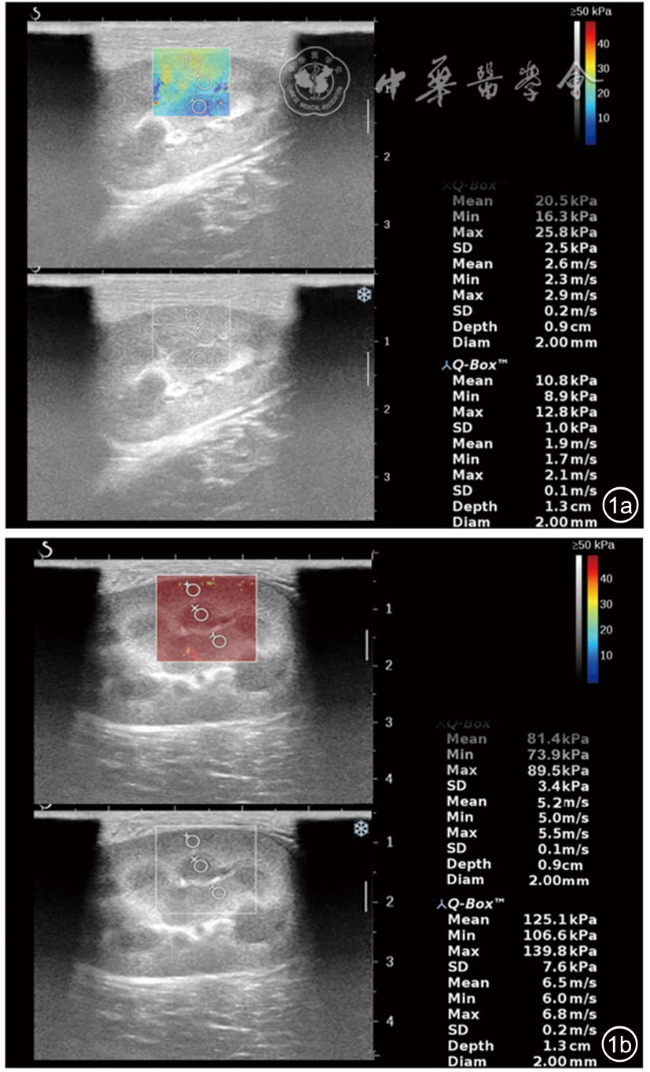

A total of 20 New Zealand White rabbits were used as the study subjects. At 2 hours after ligation of the left renal vein, Young's modulus was measured and compared across different sides (healthy side vs affected side), anatomical locations (upper pole vs mid portion vs lower pole), and organizational structures (cortex vs medulla vs renal sinus) of the kidney. The point-biserial correlation coefficient was employed to analyze the correlation between Young's modulus in various renal regions and the status of acute renal vein occlusion. The intraclass correlation coefficient (ICC) was used to assess the reproducibility of the Young's modulus measurements.

Regarding anatomical locations, in the healthy side group, the differences in Young's modulus were statistically significant between the upper pole and mid portion, and between the mid portion and lower pole (P<0.05). In the affected side group, no statistically significant differences in Young's modulus were observed among the upper pole, mid portion, and lower pole (P>0.05). Regarding organizational structures, in the healthy side group, the differences in Young's modulus were statistically significant between the cortex and renal sinus, and between the medulla and renal sinus (P<0.05). In the affected side group, the differences in Young's modulus among the cortex, medulla, and renal sinus were all statistically significant (P<0.05). Three-way ANOVA revealed that the three-way interaction effect (acute renal vein occlusion status × anatomical location × organizational structure) was not statistically significant (F=1.575, P=0.190). The Young's modulus values in the affected side group were consistently higher than those in the healthy side group for identical anatomical locations and organizational structures, and all these differences were statistically significant (P<0.05). Among these comparisons, the mid-portion cortex demonstrated the most prominent effect size (Cohen's d=2.770), eexhibited the strongest correlation with acute renal vein occlusion (r=0.867), and showed the optimal measurement reproducibility (ICC=0.987).

Renal elasticity in normal kidneys shows regional heterogeneity and undergoes remodeling under pathological conditions. Acute renal vein occlusion causes a significant increase in stiffness, identifying the mid-portion cortex as the optimal diagnostic region.